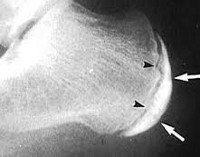

Чаще всего для оценки состояния больного применяют рентген. Это наиболее доступный и достаточно показательный метод диагностики. С его помощью можно определить неоднородность структуру костной ткани, возможные места размягчения кости, заново формирующееся губчатое вещество в разных частях пятки.

Рентгенологические признаки болезни Шинца в острой форме определяются в виде отделения осколков, образующих свободное пространство между апофизом и пяточной костью.

Диагностика состоит со сбора анамнеза, изучения клинической симптоматики и рентгенологических признаков.